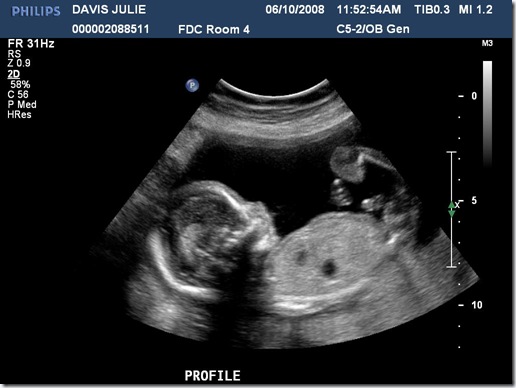

We went in for our first ultrasound today. It was a fun experience getting to see our first glimpses of the little life that is growing inside Julie’s belly. The ultrasound equipment at Winnie Palmer hospital is much better than when we had ultrasounds with our two daughters. But that was several years ago also. Seeing our baby’s little fingers, arms, heartbeat and all of the movements was a really neat experience. We also found out that we are having a little boy! We were all kinda hoping for that. Laurel and Marybeth were running around quoting a line from “Lady and the Tramp“…”Oh boy, it’s a boy! Oh boy, it’s a boy! Oh boy, it’s a boy!”

So…what does our baby look like now? Here are the five pics the hospital gave us (three are after the break). Also…if you don’t want to see the proof of “boyhood”, avoid the last picture.